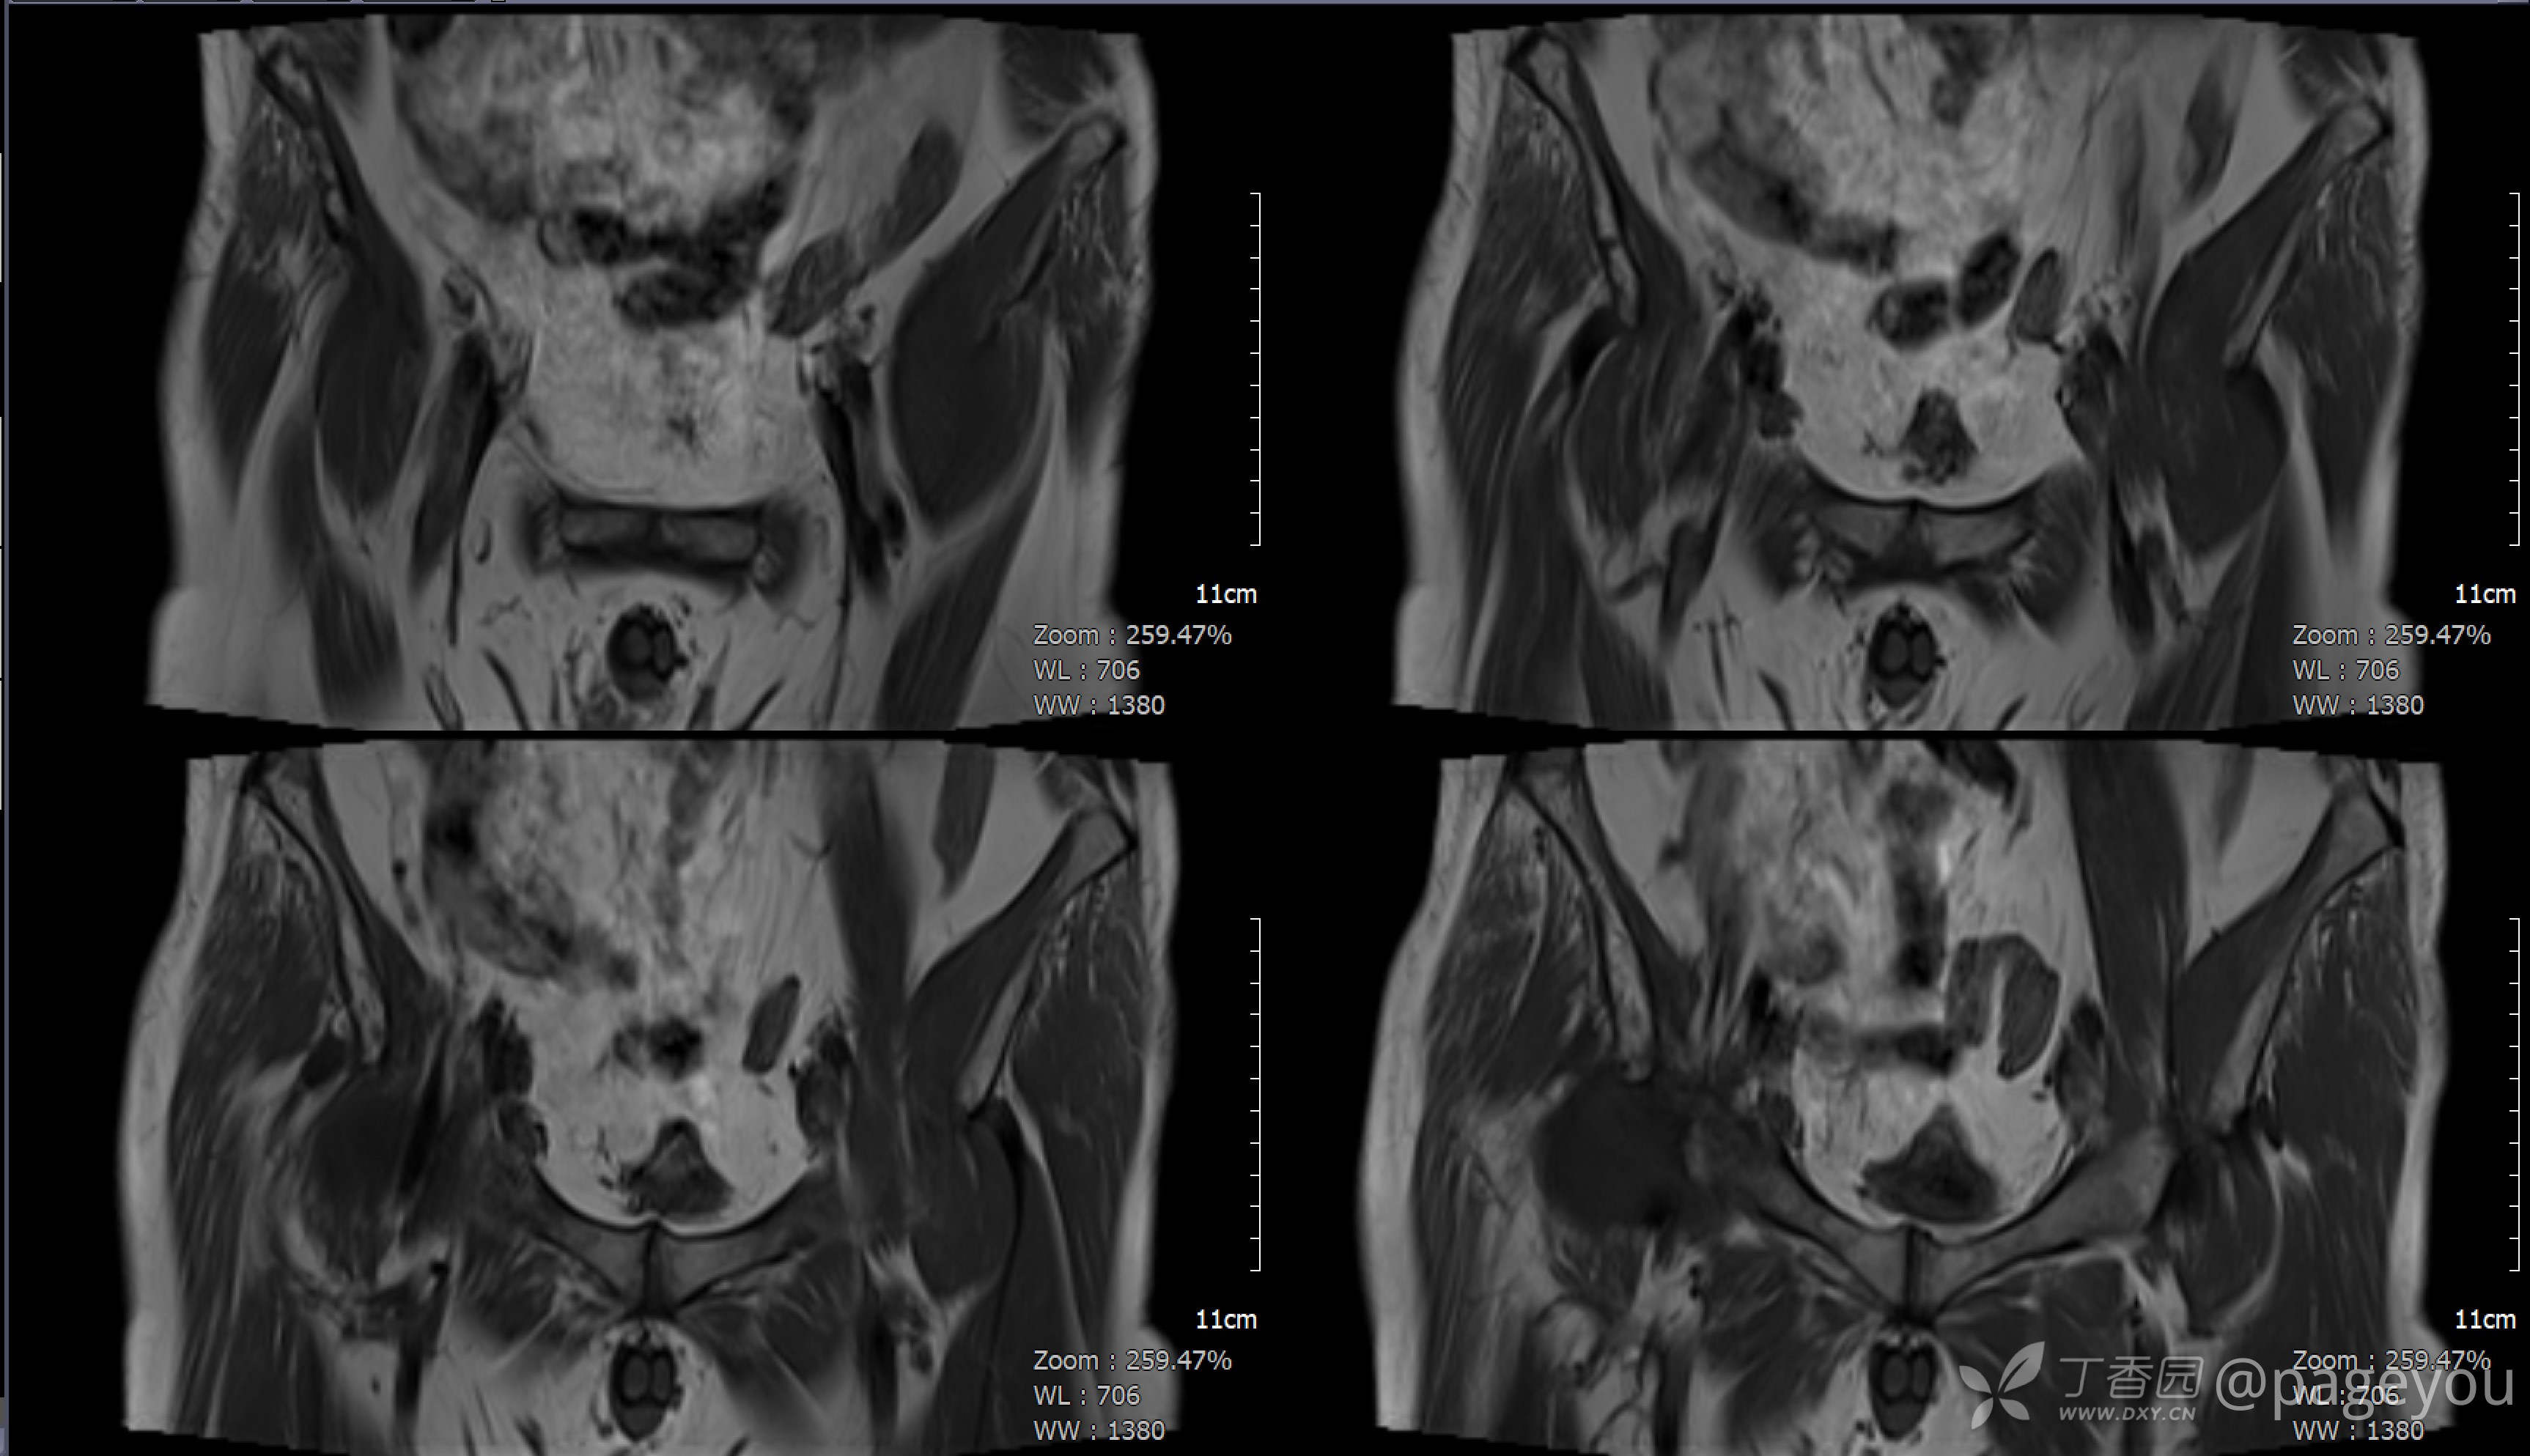

入院查腰椎MRI: